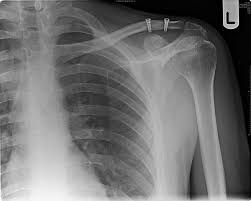

An acromioclavicular joint separation, or ac separation, is a very frequent injury among physically active people.in this injury the clavicle (collar bone) separates from the scapula (shoulder blade). Tears in the ac ligament and the nearby coracoclavicular ligaments, which connect the shoulder blade to the clavicle, cause the collarbone to dislocate. Grade i is slight displacement of the joint, and a badly stretched or partially torn ac ligament. In this case, the collarbone typically angles slightly out of place. Recommended treatment is much like in grades 1 and 2, with a period of immobilization followed by movement to restore shoulder motion and strength.

Tears of the glenoid rim often occur with other shoulder injuries, such as a dislocated shoulder (full or partial dislocation). Tibial spine avulsion acl injury In this case, the collarbone typically angles slightly out of place. It is commonly caused by a fall directly on the point of the shoulder or a direct blow received in a contact sport. Grade ii — the acromioclavicular ligament is completely torn and the coracoclavicular ligament is partially torn. This may take time with a grade 2 ac joint injury. An acromioclavicular joint separation, or ac separation, is a very frequent injury among physically active people.in this injury the clavicle (collar bone) separates from the scapula (shoulder blade). In a grade 3 sprain, the ac joint becomes completely separated. Do not get ahead of yourself. If the ligaments in the ac joint are torn, the condition is more severe (grade 2). Frequently results in a small, permanent bump over the top of the shoulder at the ac joint. Consider shoulder bracing and shoulder ice packs for icing, protecting and resting the deltoid. Although most people think of the shoulder as a single joint between the upper arm bone (humerus) and the torso, the shoulder actually has several smaller joints outside the arm bone's socket.

Brighton and sussex university trust started its physiotherapy led virtual fracture clinic in september 2013. The injury results from a fall onto the point of the shoulder and can be mild, moderate or severe.in a mild or moderate separation, the ligaments involved are stretched. And while performing the deadlift, be sure to place the bar back onto the floor with control — rather than banging it to the floor, since having control is better for the shoulder and back structures. For people with grade 3 ligament injuries usually they can return to work within four weeks. In grade 3 injuries, although the two ligaments are torn and the joint may be significantly disrupted, no attempt is made to reconstruct the ligaments or restore the joint to its normal architecture. A grade 2 separation refers to a rupture of the ac ligament, while a grade 3 separation refers to ruptures of both the ac and the nearby coracoclavicular ligaments. Tears in the ac ligament and the nearby coracoclavicular ligaments, which connect the shoulder blade to the clavicle, cause the collarbone to dislocate. Within one to two weeks most people are able to move their shoulder again without discomfort after suffering from grade 1 or 2 tears, although it can take up to six to eight weeks to return to normal athletic activity. An ac joint injury will either be a minor injury (grade 1 or grade 2), or a major injury (grade 3, grade 4, or grade 5). At the word tear, many envision massive damage and inevitable surgery to repair it or stitch it up.and while surgery is, unfortunately, often the only treatment offered, the truth is, most tendon and ligament tears aren't really extreme enough to require invasive orthopedic surgery as there are nonsurgical interventional. Grade 3 (severe) a complete tear of the ligament resulting in severe pain, extensive bleeding, and swelling. Frequently results in a small, permanent bump over the top of the shoulder at the ac joint. It is commonly caused by a fall directly on the point of the shoulder or a direct blow received in a contact sport.

A grade 2 injury will involve complete rupture of the acromioclavicular ligament and partial tear of the coracoclavicular ligament. It has the normal separation of <4mm. Finding out that you have a torn tendon or ligament can be concerning. Types of ac joint injuries. Recommended treatment is much like in grades 1 and 2, with a period of immobilization followed by movement to restore shoulder motion and strength. Which are not attached to the joint and lie away from the joint. Tearing to ac joint ligaments and other ligaments attached to the collarbone can result in a complete dislocation of the ac joint (grade 3). The athlete is usually unable to bear weight on the limb.

The ac gap is >5mm.